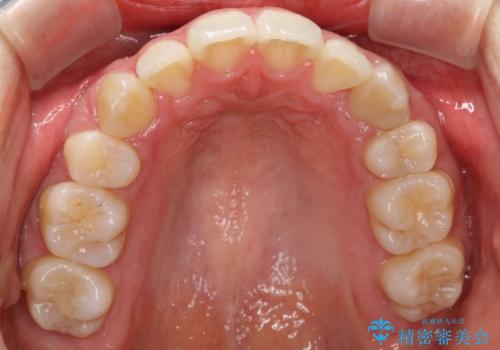

歯並びがコンプレックスで歯を見せて笑うことができなかったとのことですが、歯並びがよくなり、口元を気にせずに笑えるようになったと喜んでいただきました。

重度のガタガタ ハーフリンガルによる目立たない抜歯矯正

目立たない装置をご希望でしたので、上下左右の歯を1本ずつ抜歯してハーフリンガルでの矯正を行いました。